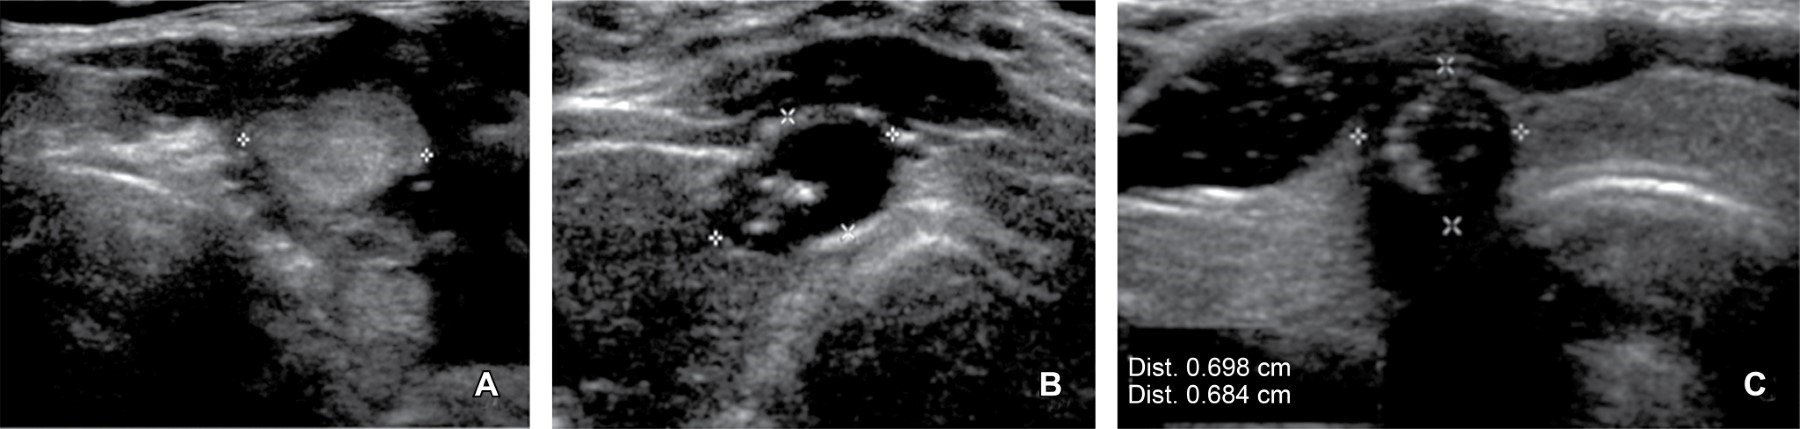

De 100% (29) de casos con resultado histopatológico de malignidad, 82.8% (24) presentaron datos ultrasonográficos que requirieron BAAF por cumplir con parámetros sugestivos de malignidad (Figura 1) y 17.2% (5) no cumplían datos para sugerir BAAF; entre estos cinco pacientes se engloban a los nódulos que por tamaño no cumplieron criterio para BAAF y, por TI-RADS-ACR, se hubiera sugerido seguimiento antes de cualquier procedimiento invasivo (Figura 2).

Entre los hallazgos por ultrasonido observamos que la mayor incidencia en los nódulos con resultado de malignidad fueron la composición sólida, la ecogenicidad que osciló entre hipoecoico y marcadamente hipoecoico, el margen lobulado o irregular y la presencia de macro y microcalcificaciones. Sin embargo, el dato con menor significancia fue la forma, la cual no tuvo ninguna diferenciación específica; se menciona esto porque es un dato al cual TI-RADS-ACR le otorga una alta calificación de tres puntos, llevando al nódulo más alto que ancho a una clasificación mayor. Es un dato que requerirá estudiarse de forma particular para mejorar los parámetros de clasificación.